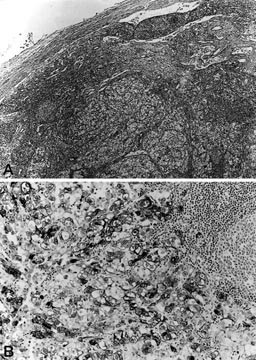

A, The tumor cells exhibit a round, often nucleolated, nucleus with abundant cytoplasm, partially clear but with interspersed fluffy eosinophilic areas. B, In other areas, particularly in Case 4, a more pronounced eosinophilia of the cytoplasm can be observed. Occasional multinucleated giant cell are present. C, Abundant brown pigment is evident in the cytoplasm of a fraction of neoplastic cells in Cases 2 and 3. D, the neoplastic cells are S-100 negative and infiltrate a nerve that is S-100 positive.

Coagulative necrosis was a prominent feature and appeared as multiple foci of variable size and tumor emboli were seen in lymphovascular spaces at the periphery of the tumor in all cases. Abundant brown pigment was evident in the cytoplasm of a fraction of neoplastic cells (about 10%), as well as in macrophages in Cases 2 and 3. This pigment was positive with Fontana-Masson stain, suggesting its melanin nature (Fig. 2C). No pigment was present in Cases 1 and 4. Only rare mitotic figures could be found. An interspersed component of adipose cells or abnormal thick-walled blood vessels was not identified. The tumor cells contained abundant intracytoplasmic periodic acid-Schiff-positive, diastase-sensitive glycogen. No diastase-resistant periodic acid-Schiff-positive crystalloid structures could be identified. Reticulin fibers surrounded individual cells, and, occasionally, small nests of cells.

The lymph nodes in Cases 1 and 2 showed metastatic deposits of the neoplasm (Fig. 3A), whereas Case 4 showed a metastatic deposit in the right ovary.

The immunocytochemical profile of the tumors was similar, and is summarized in Table 1. The cells were negative for epithelial markers (CAM 5.2, KL1, AE1, AE3, EMA), vimentin, chromogranin-A, S-100 protein (Fig. 2D), desmin, myosin, and muscle-specific actin. They showed strong granular staining for the melanogenesis-related markers HMB45 (Fig. 3B) and, in two cases, for MART-1). The Mib1 (Ki-67) was positive in a fraction of the neoplastic cells (range, 2 to 8% positive).